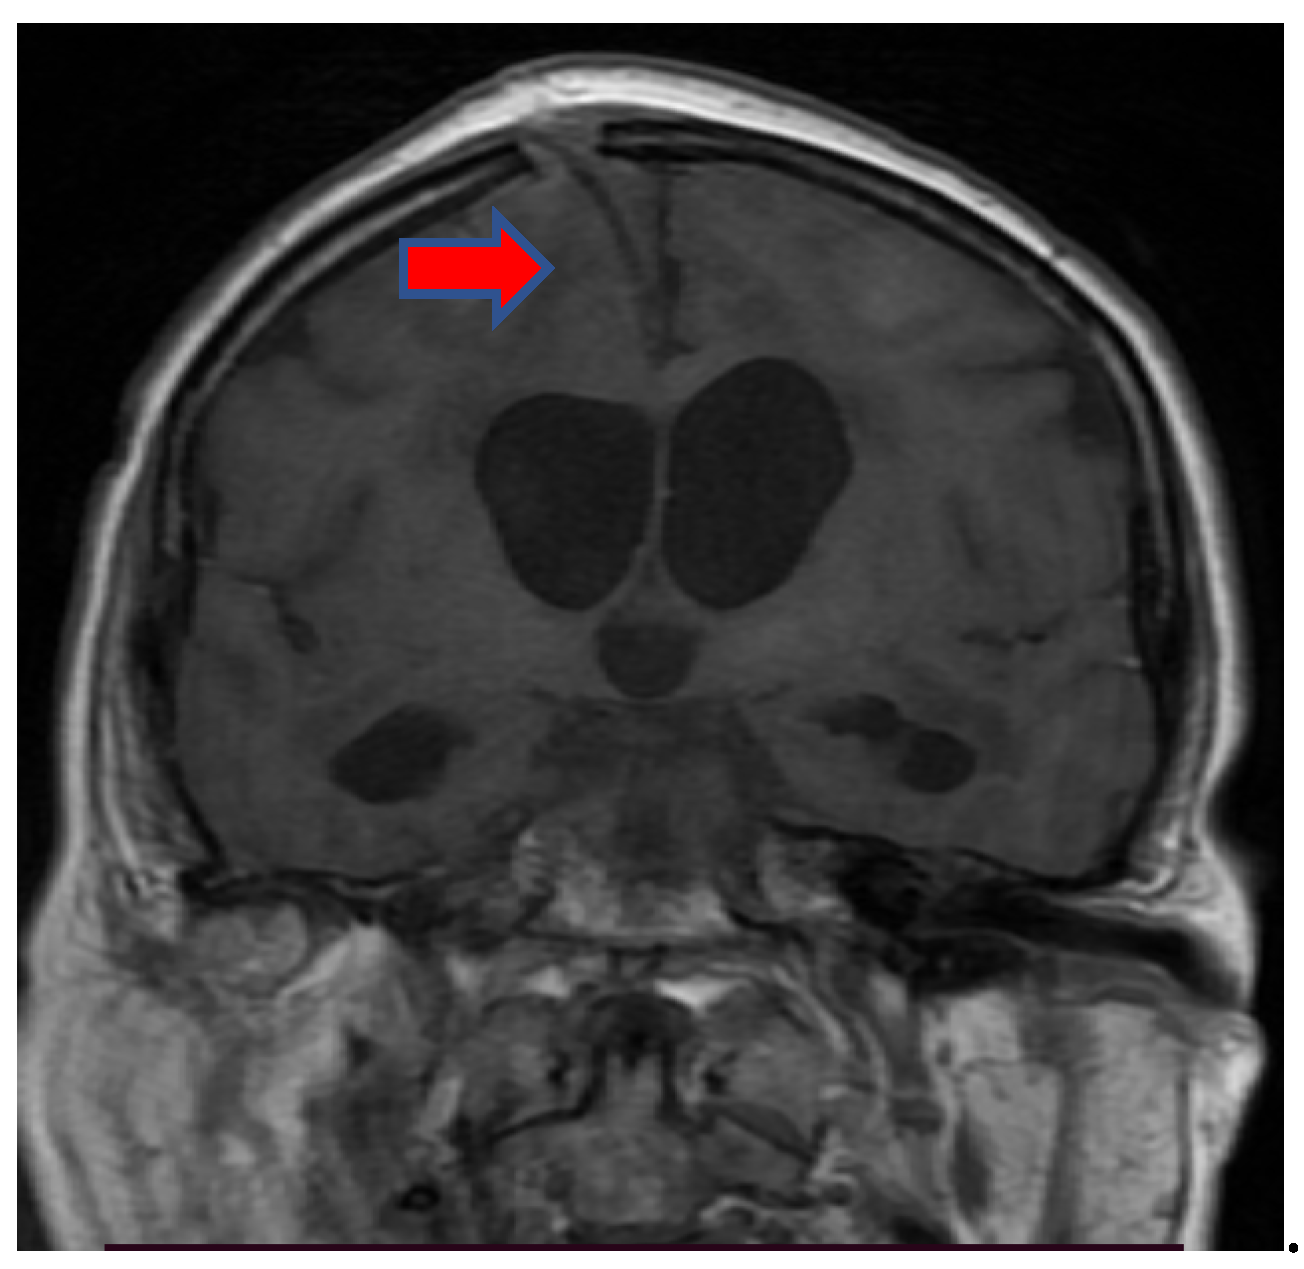

3.3. Neuroimaging